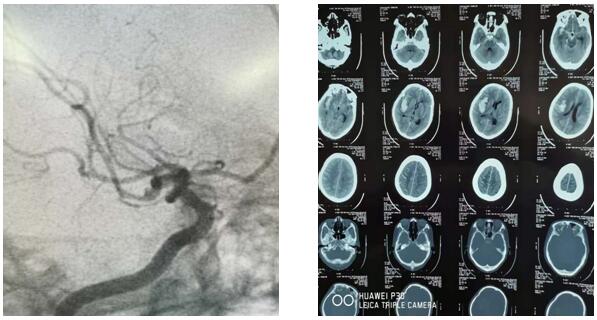

2019年6月7日10時30分,延安大學咸陽醫(yī)院神經外科二病區(qū)收治了一顱腦動脈瘤破裂出血患者,入院時頭顱CT示右側顳葉腦出血,量約30ml,破入蛛網膜下腔,由于出血部位及形態(tài)與常見的高血壓腦出血不同,主管醫(yī)師王海波考慮動脈瘤出血可能性大,建議行腦血管造影檢查,發(fā)現(xiàn)患者顱腦右側大腦中動脈下干近端血泡樣動脈瘤。瘤體大小為1mm*2mm,經科主任劉小雷、責任總醫(yī)師游文良及全科醫(yī)師討論后,判定出血原因為“血泡樣”動脈瘤破裂。手術組最終決定在顯微鏡下施行外科動脈瘤夾閉手術,同時清除血腫。由于“血泡樣”動脈瘤術中發(fā)生破裂大出血可能性較大,手術風險也隨之加大。相對血管內介入治療,此類手術為高難度、高風險的手術。需要更加扎實的血管解剖、顱底解剖知識和嫻熟的手術技巧。因此動脈瘤夾閉手術也被神經外科醫(yī)師們譽為“刀尖上的舞蹈”。 而這次的舞蹈是在最容易破裂大出血的“血泡”上表演。

此時患者已經陷入深昏迷,情況緊急,時間就是生命,已經沒有再多的時間考慮了,科主任劉小雷、責任總醫(yī)師游文良再次組織全科醫(yī)師討論,詳細向家人告知目前情況,最終決定急診開顱手術。如何避免術中發(fā)生大出血,成為擺在神經外科二病區(qū)團隊面前的最大問題。劉小雷主任,游文良責任總醫(yī)師帶領的神經外科團隊經過慎重、反復討論,決定由翼點入路夾閉動脈瘤并清除血腫。手術在全麻下進行。首先要通過腦自然間隙找到大腦中動脈下干,仔細分離,暴露動脈瘤,予以夾閉。整個過程都必須經過腦自然間隙進入顱腦深部,保證腦組織、血管和神經的完好,最后清除血腫,血腫腔嚴密止血。手術圓滿完成。目前患者處于恢復期,患者神志清,言語流利,思維清楚,除左側肢體肌力稍減弱外,其他功能均正常,在家人攙扶下可以慢慢行走。